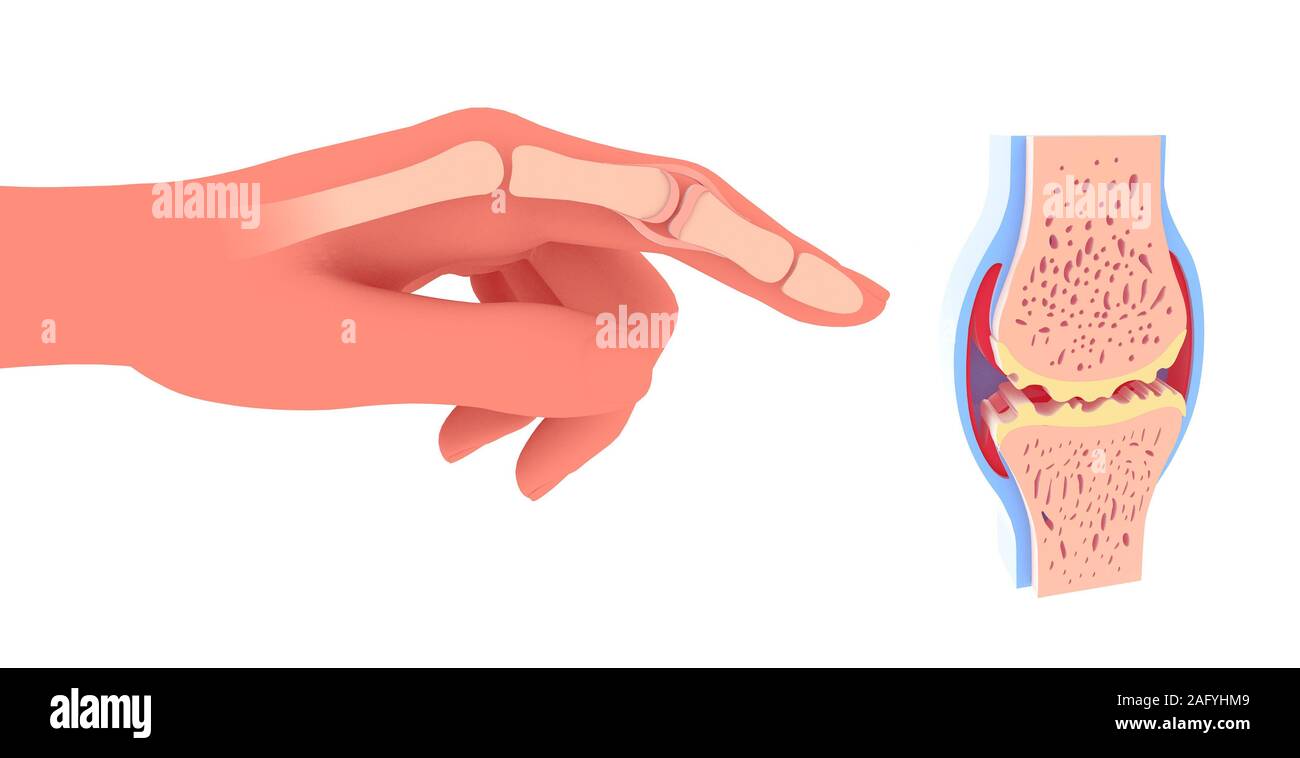

3d illustration of synovial joint. Next to the graphic representation of a hand placing the joint, front view on white background. Stock Photohttps://www.alamy.com/image-license-details/?v=1https://www.alamy.com/3d-illustration-of-synovial-joint-next-to-the-graphic-representation-of-a-hand-placing-the-joint-front-view-on-white-background-image336823446.html

3d illustration of synovial joint. Next to the graphic representation of a hand placing the joint, front view on white background. Stock Photohttps://www.alamy.com/image-license-details/?v=1https://www.alamy.com/3d-illustration-of-synovial-joint-next-to-the-graphic-representation-of-a-hand-placing-the-joint-front-view-on-white-background-image336823446.htmlRF2AFYHMP–3d illustration of synovial joint. Next to the graphic representation of a hand placing the joint, front view on white background.

3d illustration of synovial joint. Next to the graphic representation of a hand placing the joint. Stock Photohttps://www.alamy.com/image-license-details/?v=1https://www.alamy.com/3d-illustration-of-synovial-joint-next-to-the-graphic-representation-of-a-hand-placing-the-joint-image336823437.html

3d illustration of synovial joint. Next to the graphic representation of a hand placing the joint. Stock Photohttps://www.alamy.com/image-license-details/?v=1https://www.alamy.com/3d-illustration-of-synovial-joint-next-to-the-graphic-representation-of-a-hand-placing-the-joint-image336823437.htmlRF2AFYHMD–3d illustration of synovial joint. Next to the graphic representation of a hand placing the joint.

3d illustration of synovial joint with osteoarthritis. Next to the graphic representation of a hand placing the joint. Stock Photohttps://www.alamy.com/image-license-details/?v=1https://www.alamy.com/3d-illustration-of-synovial-joint-with-osteoarthritis-next-to-the-graphic-representation-of-a-hand-placing-the-joint-image336823433.html

3d illustration of synovial joint with osteoarthritis. Next to the graphic representation of a hand placing the joint. Stock Photohttps://www.alamy.com/image-license-details/?v=1https://www.alamy.com/3d-illustration-of-synovial-joint-with-osteoarthritis-next-to-the-graphic-representation-of-a-hand-placing-the-joint-image336823433.htmlRF2AFYHM9–3d illustration of synovial joint with osteoarthritis. Next to the graphic representation of a hand placing the joint.